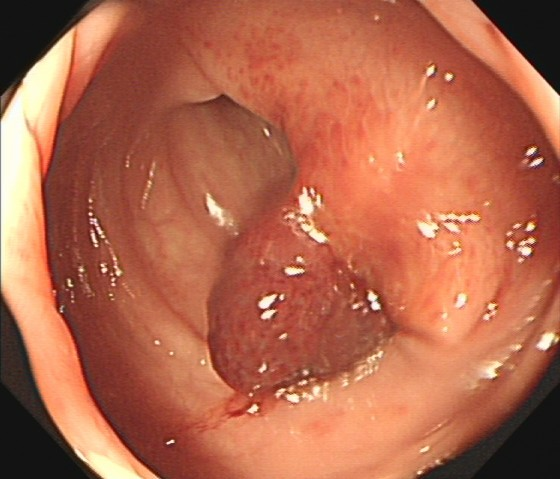

(3)邓先生(54岁,乙状结肠息肉,图3)

肠镜一照,息肉现形!形态各异的大肠息肉,离癌有多远?(图3)

图3

病理诊断:(乙状结肠)管状腺瘤。

解读:这是最常见的腺瘤类型。若未发现高级别瘤变或癌变,属于相对早期的癌前病变。但放任不管,其癌变风险随时间推移而增加。距离癌:潜在风险,癌前病变早期。